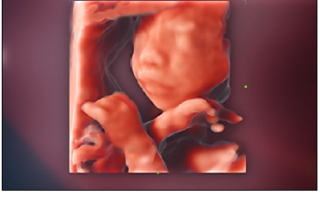

Mindray Ultrasound Consona N9